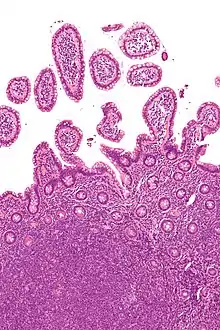

![]() | |

| Micrograph showing mantle cell lymphoma (bottom of image) in a biopsy of the terminal ileum. H&E stain. | |